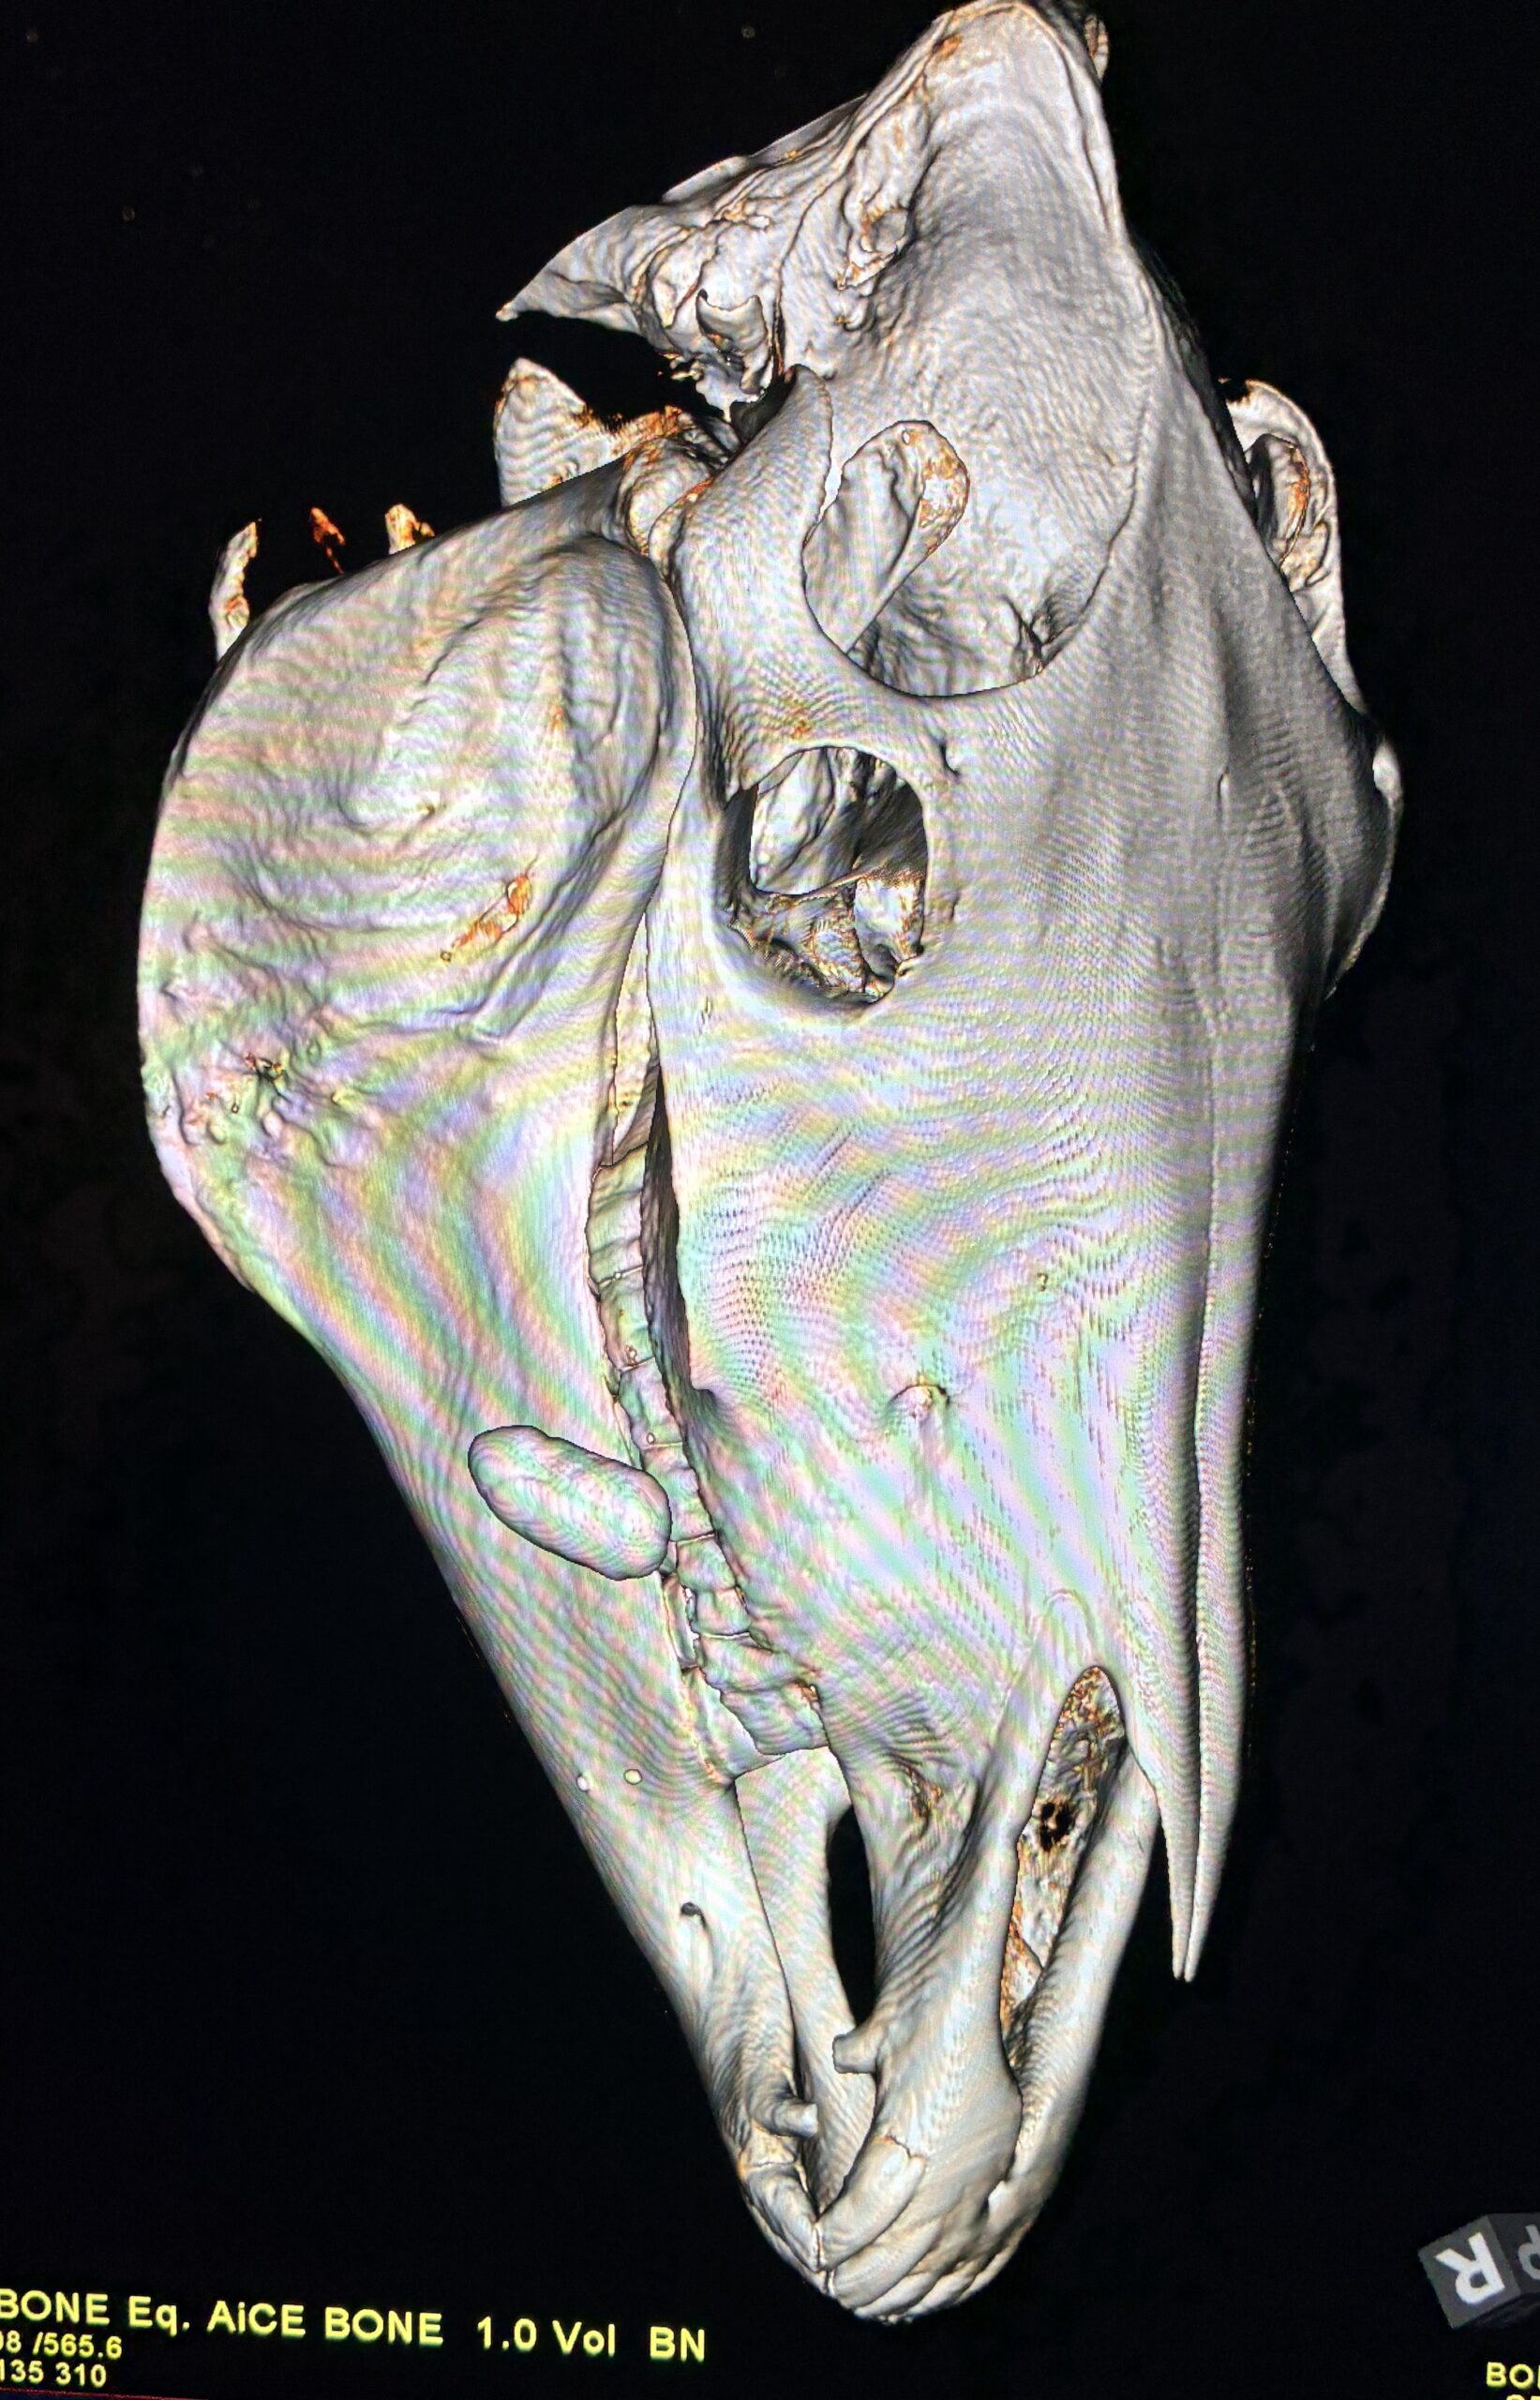

The scan showed a large oval structure, of some 2x3x6cm in the soft tissue of Joe Juice’s cheek.

The stone can be seen on the left of the scan image

“Joe Juice was a model patient for our standing CT training,” said Mathieu Spriet, director of imaging services at the VMTH. “His sialolith was definitively diagnosed with the standing CT, giving surgeons a clear and concise assessment of the growth. This equipment’s ability to determine injuries and disease without full anesthesia is already proving to be tremendously valuable for our patients.”